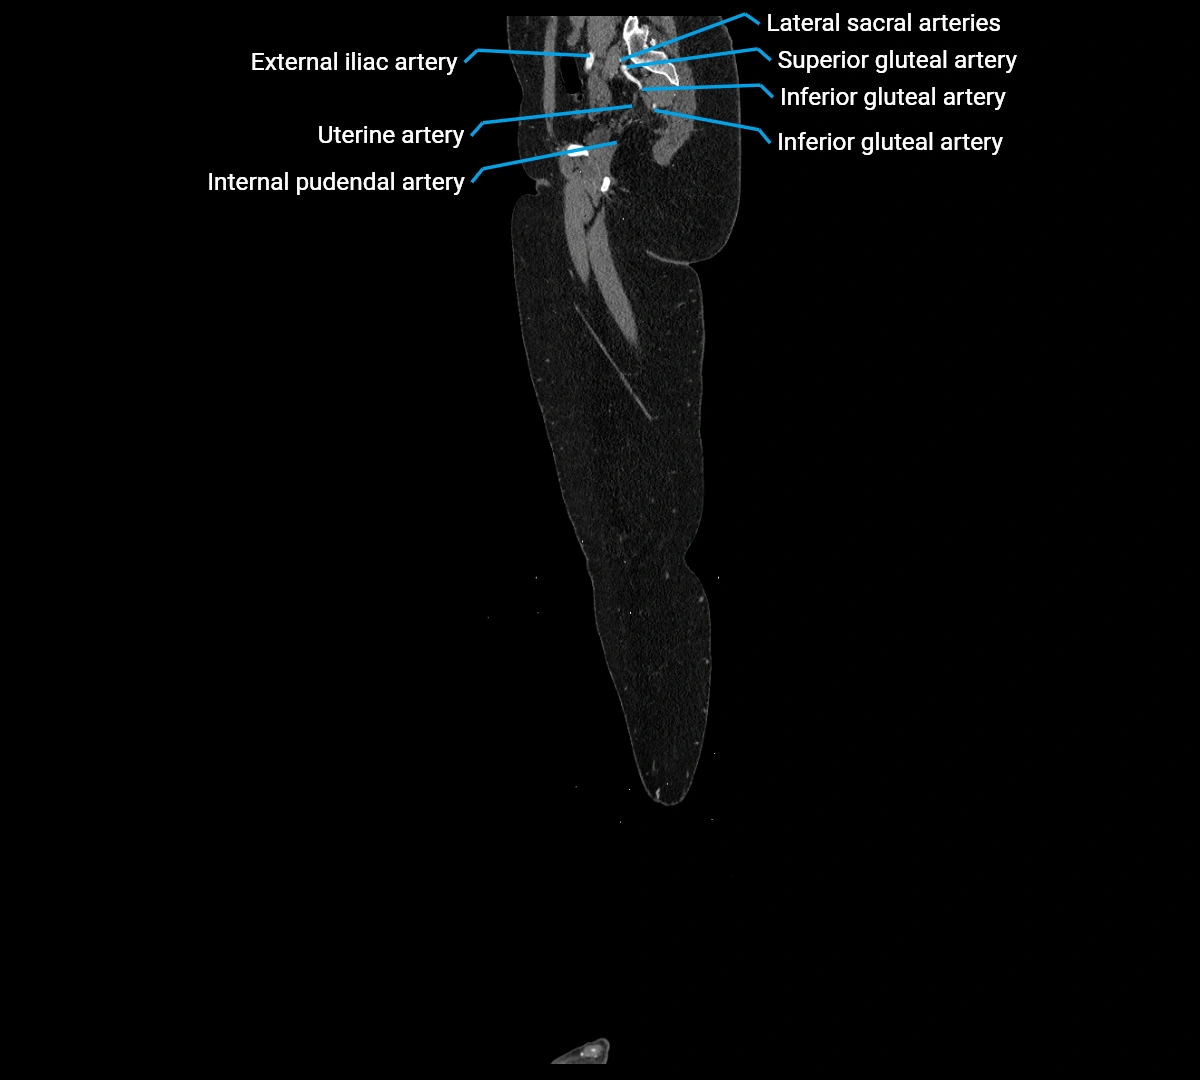

CT Appearance

Contrast-enhanced CT (CTA):

• Gold standard for abdominal aortic imaging

• Provides excellent detail of lumen, wall, aneurysm, thrombus, and branch vessels

• Multiplanar and 3D reconstructions help in aneurysm measurement, stent graft planning, and dissection evaluation

• Detects acute rupture, traumatic injury, or occlusion with high sensitivity

CT images

image